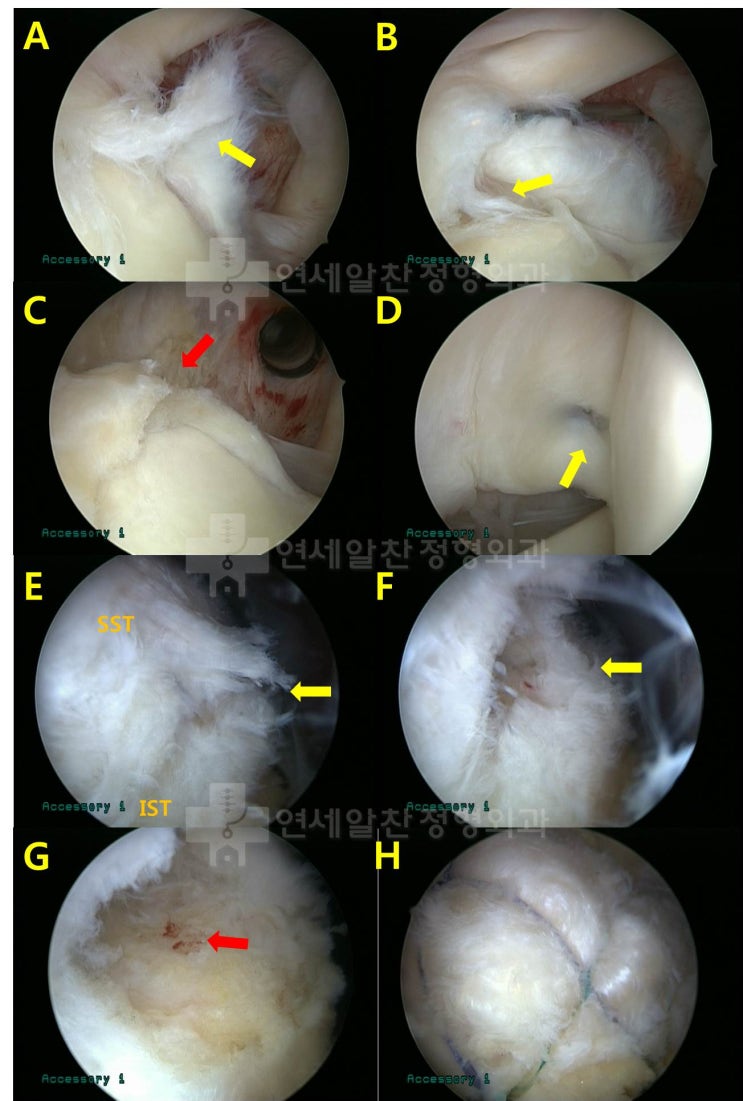

어깨 회전근개 파열 : 보다 단단하게 봉합하는 이열봉합법

안녕하세요. 정형외과 전문의 이동규 입니다. 오늘은 회전근개 파열에서 관절경 수술시 더 단단하게 봉합하...

2021. 11. 25.